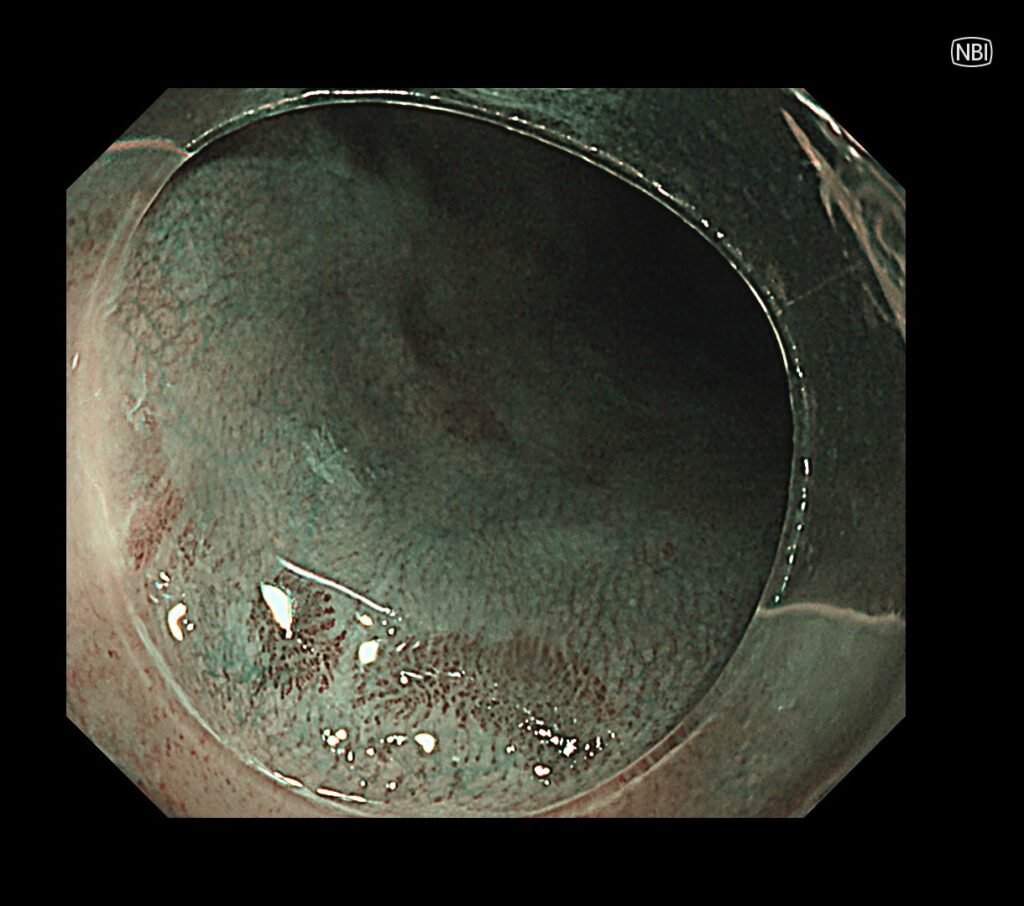

通常観察では周囲粘膜より、やや茶食の領域が散見されています。

この時点で、入念に食道癌の発見に集中します。

NBI拡大モードで癌血管を視認。